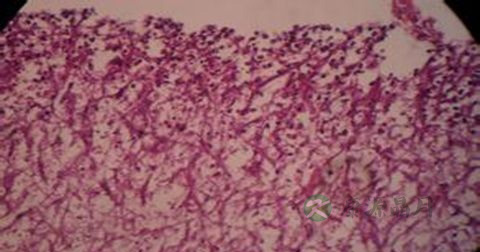

1、咯血:肺结核咯血原因多为渗出和空洞病变存在或支气管结核及局部结核病变引起支气管变形、扭曲和扩张。肺结核患者咯血可引起窒息、失血性休克、肺不张、结核性支气管播散和吸入性肺炎等严重合并症。